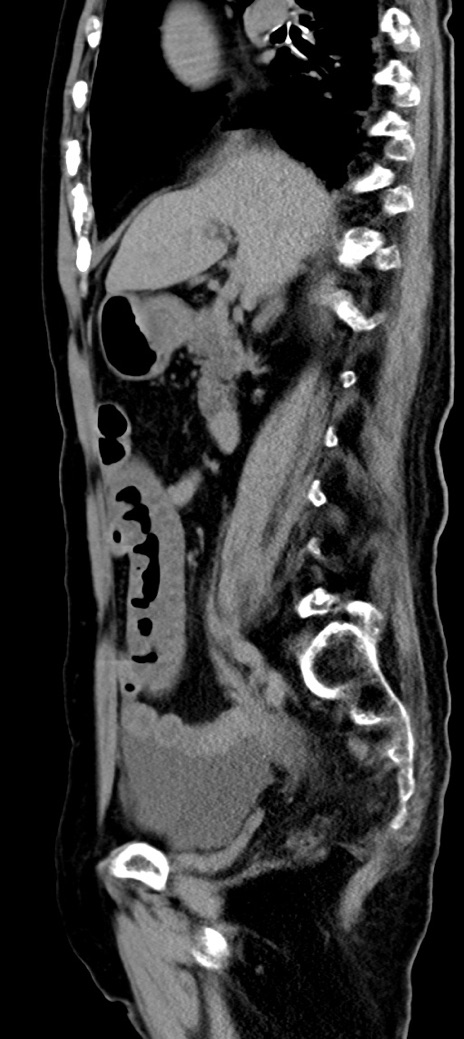

横断像

他院CT